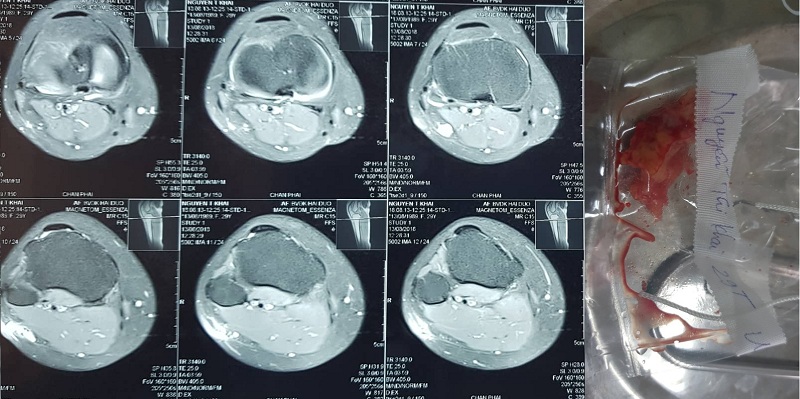

U cuộn mạch: tổn thương hiếm gặp

Cuộn mạch (neuromyoarterial glomus) là một cấu trúc giải phẫu nằm dưới da, có ở nhiều vị trí trên cơ thể cũng như trong các cơ quan. U cuộn mạch là một cấu trúc bất thường, phát triển từ cuộn mạch.